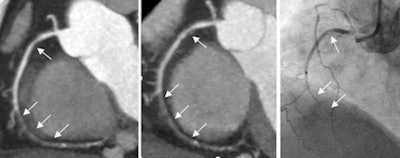

61-year-old woman (body weight, 65 kg; heart rate, 57 beats/min) with suspected coronary artery disease underwent two coronary CTA acquisitions using prospectively electrocardiogram-triggered high-pitch spiral technique. Multiple high-grade stenosis (local nearly occlusive) and noncalcified plaque of the right coronary artery are shown on maximum-intensity projection in both FBP (left) and IR (middle) series. The lesion was confirmed by subsequent coronary catheter angiography (right). The dose-length products were 62 and 31 mGy-cm for the FBP and IR protocols, respectively. Image courtesy of Dr. Bin Lu.

With FBP, the area under the receiver operator characteristics (ROC) curve was 0.903 (95% confidence interval [CI]: 0.881-0.922), compared with 0.888 (95% CI: 0.864-0.909) for iterative reconstruction on a per-segment level.

Compared with FBP, the iterative reconstruction series showed no statistically significant differences (p > 0.05) in subjective image quality analyses, despite a median dose-length product that was 52% lower with the IR protocol than the FBP protocol. Median dose-length product was 109 mGy-cm for the FBP protocol and 52 mGy-cm for iterative reconstruction.